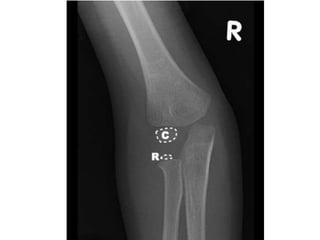

Elbow

• Appearance(Years)

• 1st- Capitulum and lateral

part of trochlea

• 5th – Head of Radius

• 6th- Medial epi. Of

humerus

• 9th- Medial part of

trochlea

• 10th- Top of Olecranon

process

• 12th- Lateral epi. Of

• Fusion

• 15th- Olecranon epiphysis

with upper end of ulna

• 16th – lateral epicondyle,

capitulum and trochlea

into one mass, and with

shaft.

• 17th- Head of radius to

shaft

• 20th – Medial epicondyle

of humerus to shaft

i. 6 years: fusion of head

with tubercles

ii. CRITOE (mnemonic): Count

1-3-5-7-9-11 for age

iii. Capitulum: 1 year

iv. Radial head: 3 years

v. Internal

(medial)epicondyle: 5

years

vi. Trochlea: 7 years

vii.Olecranon: 9 years

viii.External (lateral )

epicondyle: 11 years